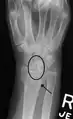

Dynamic scapholunate instability visible upon clenching the wrist